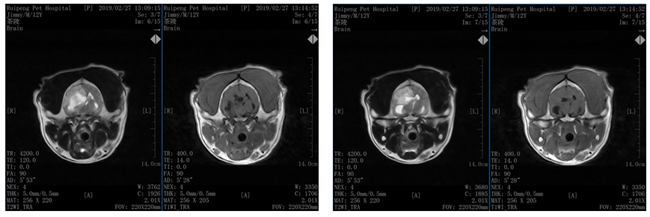

一例犬脑肿瘤的诊断(图)

2.4 MRI影像学检查

3、诊断结果

诊断为:脑肿瘤